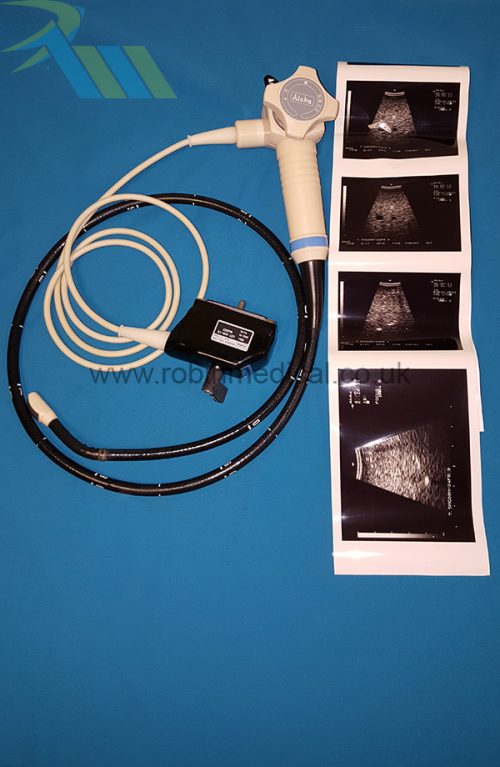

The Sonosite C11e P07161-16 is a high-performance curved-array transducer designed for the Sonosite MicroMaxx ultrasound system. With a frequency range of 8–5 MHz, it delivers exceptional imaging clarity for abdominal, pediatric, and vascular applications. Its compact 11 mm footprint makes it ideal for scanning in narrow or confined anatomical regions, while maintaining superb detail resolution. This probe offers versatility and portability in fast-paced clinical environments.

The probe functions as intended and the condition is exactly as shown in images.